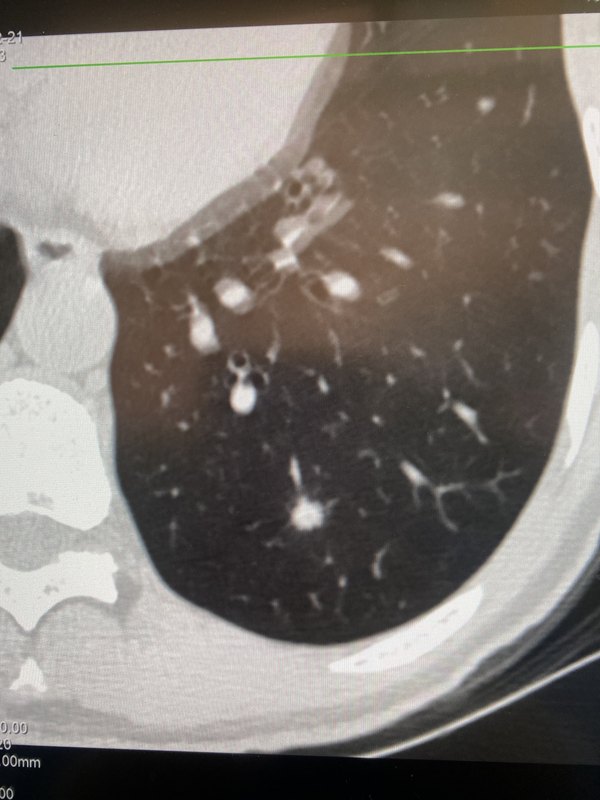

初診,左下肺孤立實(shí)性結(jié)節(jié) 2個月后復(fù)查,竟然變通俗講的“混合磨玻璃“,但是變得淡了 離初診不到半年,徹底吸收 不要急于手術(shù)切除,應(yīng)該先隨訪3到6個月,給自己一個機(jī)會,數(shù)月短期內(nèi)密度有變動的結(jié)節(jié)多半是炎性結(jié)節(jié)